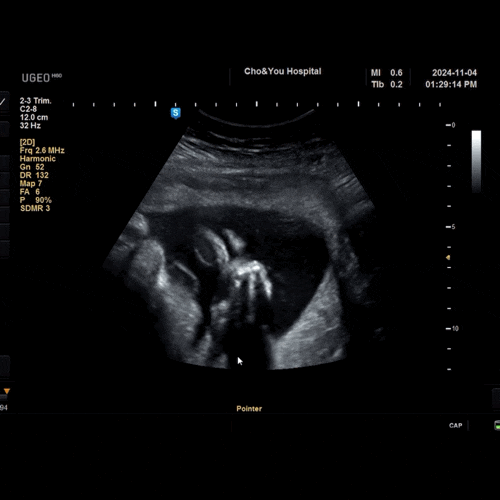

[육아] 20241227

2025.05.02